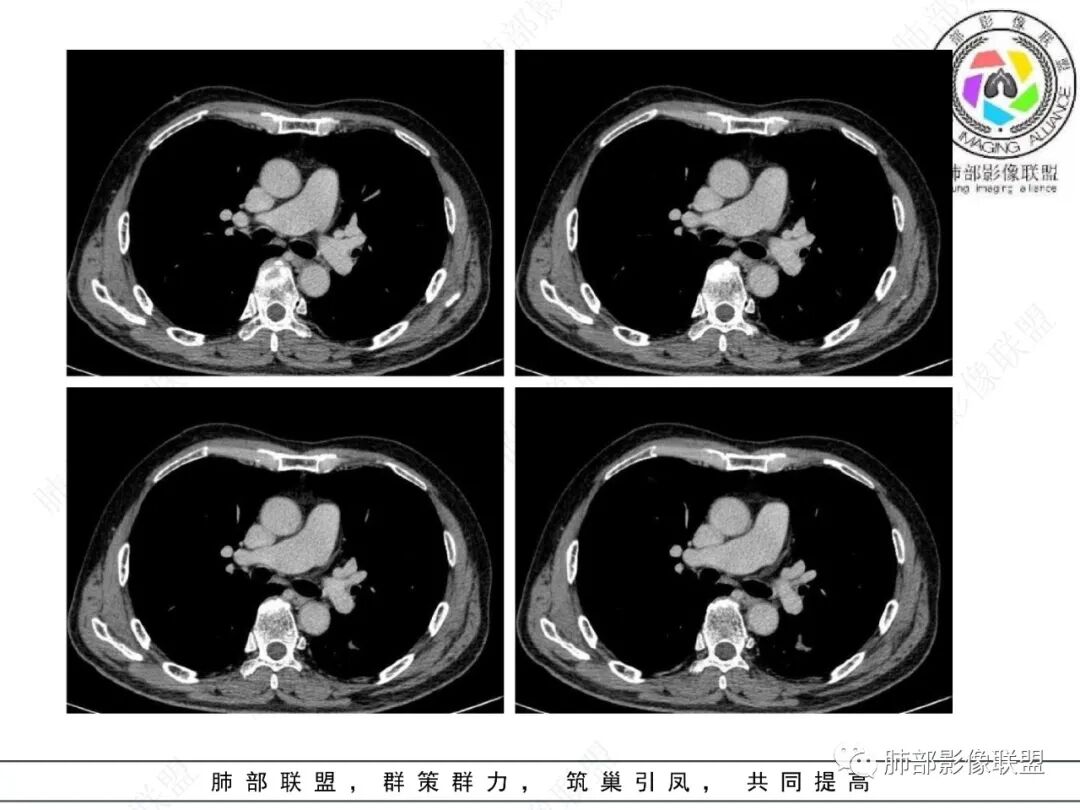

影像学表现:左肺下叶背段近叶间裂旁不规则实性密度结节影,图像未明确显示与支气管关系。边界清,整体膨隆感较明显,边缘显示分叶,偶见段毛刺,叶间胸膜“L”形牵拉凹陷,密度均匀,未见空洞或液化,也未见明显脂肪密度及钙化,轻到中度渐进性强化,未见明确蛇纹状血管应。左肺门可见多发小淋巴结影,纵隔内未见明显肿大淋巴结影。

未见明确卫星灶。

小结:老年吸烟男性,较大孤立结节影,应高度警惕新生物。病灶强化,分叶,收缩力强,应当怀疑恶性,尤其是常见的肺腺癌。尽管“大细胞癌”的病理意见出乎预料。